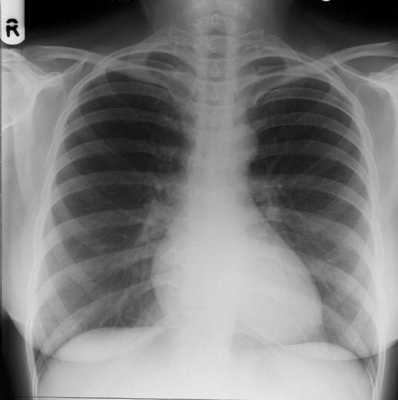

Рентгенография бывает обзорной и прицельной. Обзорные снимки, как правило, должны выполняться в двух проекциях - прямой и боковой (исследуемой стороной к кассете). На обзорных рентгенограммах грудной клетки всегда будут видны как передние, так и задние отделы ребер, ключица, лопатка, позвоночник и грудина, независимо от проекции снимка (рис. 3.1 и 3.2). Этим отличается обзорная рентгенограмма от томограммы.

Рис. 3.1. Обзорная рентгенограмма легких в прямой проекции. Норма (см. текст).